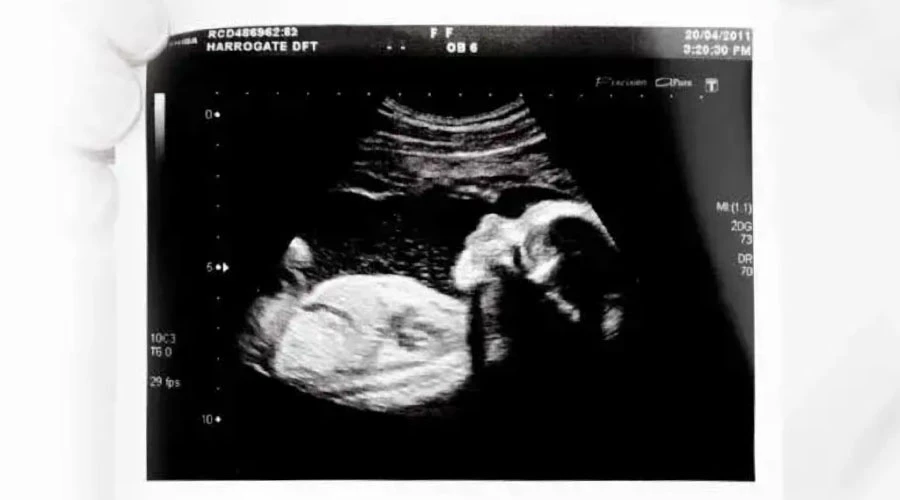

El proyecto de ley busca que antes de realizar el aborto, se realice un “ultrasonido por personal capacitado e idóneo de conformidad con las prácticas médicas estándares, a los efectos de determinar la detección de latidos fetales".

"Los médicos, personal de salud y/o sistemas de salud no podrán realizar o inducir intencionalmente un aborto o interrupción del embarazo, si se detecta un latido cardíaco del/de los feto/s o niño/s en gestación, entendido el mismo como actividad cardíaca o contracción rítmica constante y repetitiva del corazón fetal, dentro del saco gestacional", señala la propuesta legislativa.

En caso de no detectar latidos cardíacos, se deberá “repetir el estudio de ultrasonido a los efectos de confirmar el resultado negativo, con un intervalo mínimo de 72 hrs. entre el primer y el segundo ultrasonido”.

Solo tras confirmar en ambos estudios la inexistencia de latidos cardíacos fetales, se podría realizar el aborto.